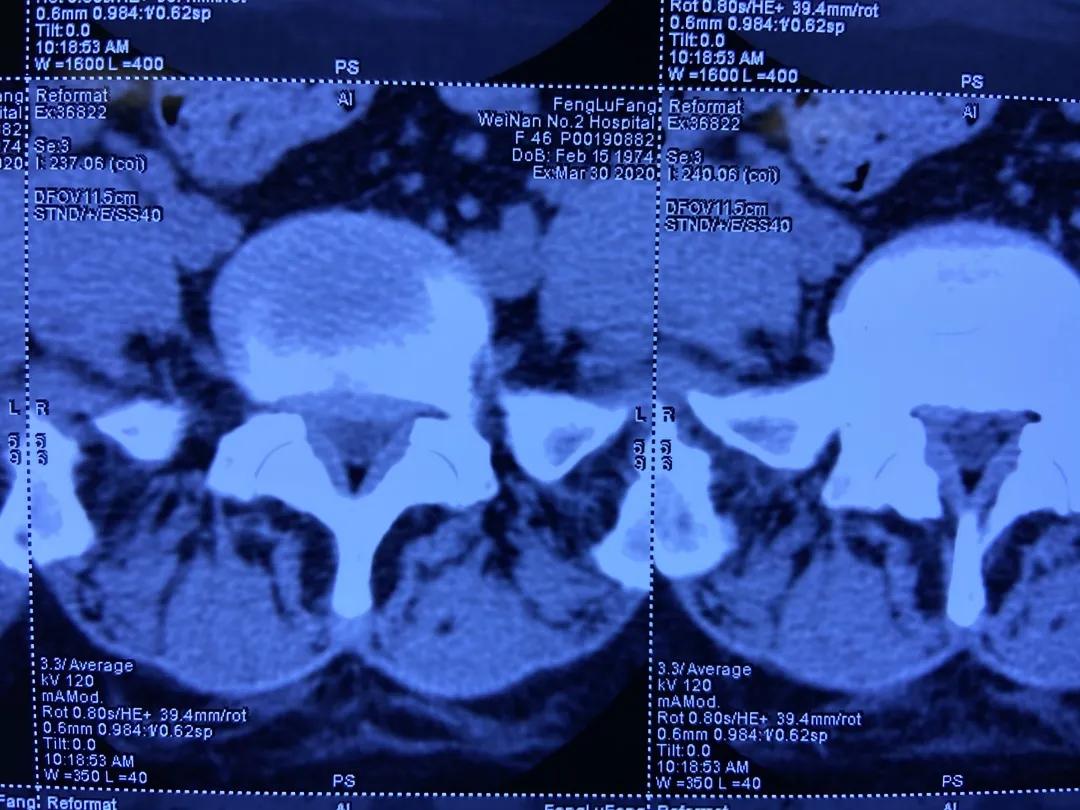

术前CT检查:L5/S1椎间盘突出,黄韧带肥厚。